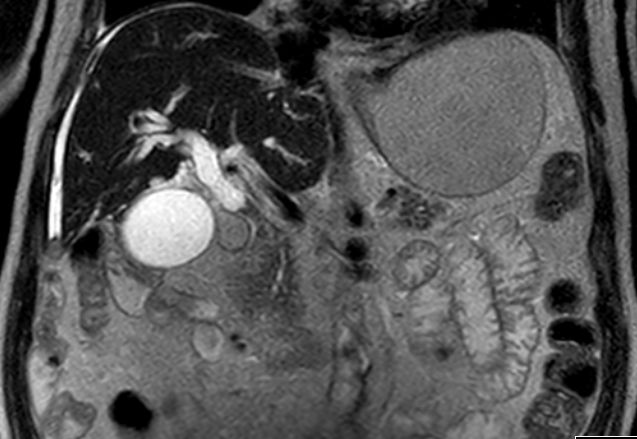

| Diagnostik | 81-jähriger Mann mit schmerzlosem Ikterus seit 14 Tagen. Das MRT zeigt einen erweiterten Gallengang mit spindelförmiger Einengung durch Gewebe im distalen Gallengang. ![]() | ||